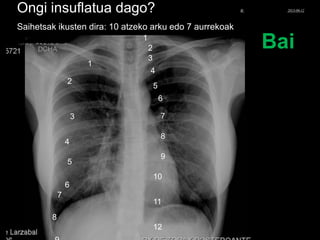

Ongi insuflatua dago?

Saihetsak ikusten dira: 10 atzeko arku edo 7 aurrekoak

Bai